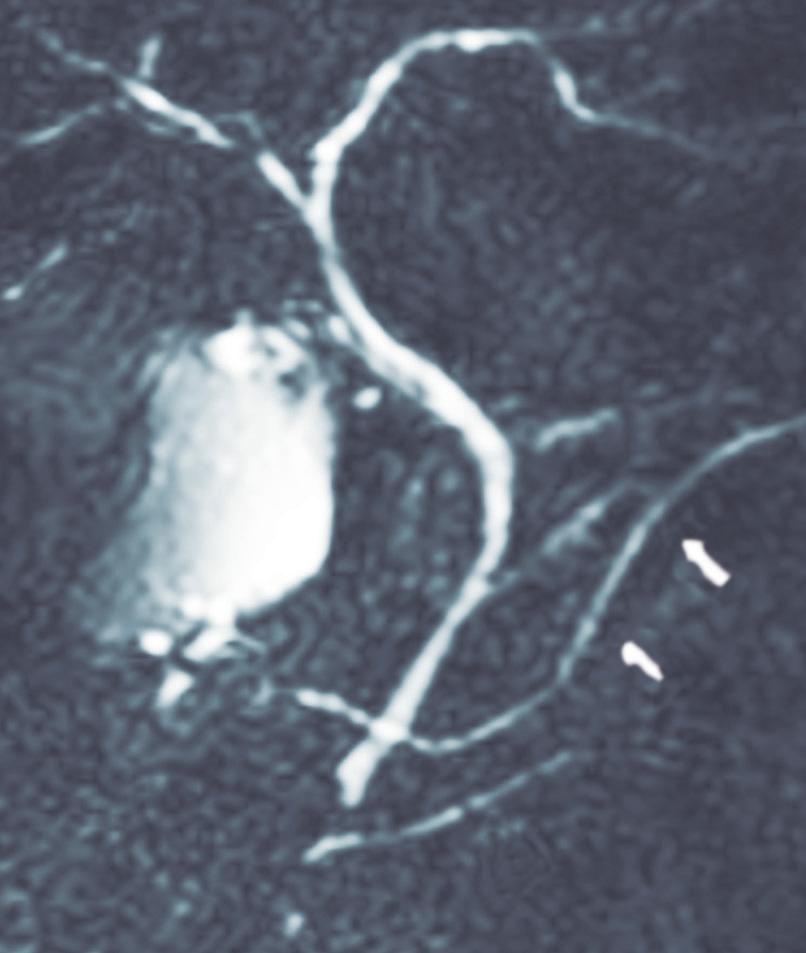

Páncreas divisum

Es la anomalía del desarrollo pancreático más frecuente, presente en 4 a 14% de la población según lo publicado en diferentes series.5

En esta condición hay una falta de fusión de los conductos del páncreas dorsal con el ventral, por

ende, la mayoría de las secreciones de la glándula desembocarán en la papila menor. Se han descripto tres subtipos de páncreas divisum. Tipo 1 o clásico, con falta completa de fusión, pudiendo identificarse ambos conductos claramente separados; tipo 2, donde el

conducto dorsal es dominante y drena en la papila menor, mientras que el conducto de Wirsung (páncreas ventral) está ausente; y tipo 3 o funcional, donde hay una rama comunicante filiforme entre ambos conductos (Figura 2). 6, 7

Los individuos con páncreas divisum suelen ser asintomáticos y diagnosticados incidentalmente en estudios de colangio-RM realizados por otros motivos (Figura 3). Se ha descripto su potencial rol como desencadenante de eventos de pancreatitis aguda (PA) y pancreatitis aguda recurrente (PAR). La hipótesis es que la papila menor, más pequeña, es insuficiente para permitir el drenaje adecuado del volumen de secreciones originadas en el páncreas corpocaudal, que habitualmente derivan hacia la papila mayor. Actualmente se acepta que la PAR es

una condición de origen multifactorial y que el páncreas divisum actúa como cofactor, habitualmente asociado a otras entidades, como son las mutaciones genéticas (genes CFTR, PRSS1). La sola presencia de páncreas divisum como “gatillo” de pancreatitis es controversial, fundamentalmente debido a que no se ha demostrado mayor prevalencia de esta condición en pacientes con PA, comparativamente con la población general.8, 9 En la colangio-RM podemos encontrar algunos elementos imagenológicos que sugieren un posible au-

Figura 3. Páncreas divisum. Colangiopancreatografía por resonancia magnética

A) Subtipo 1. Las flechas señalan al conducto pancreático principal, que drena sus secreciones en la papila menor. La cabeza de la flecha señala el conducto de Wirsung desembocando en la papila mayor. B) Subtipo 2. CPP desembocando en la papila menor en ausencia de un conducto definido del páncreas ventral. C) Subtipo 3. La flecha señala una diminuta comunicación entre los conductos del páncreas dorsal y ventral.

mento de la presión del CPP y por lo tanto una mayor influencia del páncreas divisum como factor etiológico de pancreatitis. La dilatación ductal mayor a los 3 mm y/o la presencia de una dilatación sacular en la desembocadura (Santorinicele), son hallazgos imagenológicos

que sugieren un rol en el desarrollo de eventos (Figuras 4 y 5). Por otra parte, la colangio-RM, por su gran resolución de tejidos, puede demostrar signos incipientes de pancreatitis crónica que orienten hacia el potencial impacto del páncreas divisum.10-13